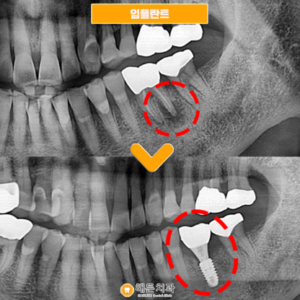

천안아산치과 치아가 탈락되면

천안아산치과 치아가 탈락되면 (치료기간 : 2022.04~ 2022.07) 안녕하세요. 오늘은 저희 천안아산치과를 내원하여어금니 뿌리 끝 염증으로 인해 임플란트 시술하신 환자분을 소개해 드릴까 하는데요. 아래 사진을 보면서 설명해 드리도록 하겠습니다. .…